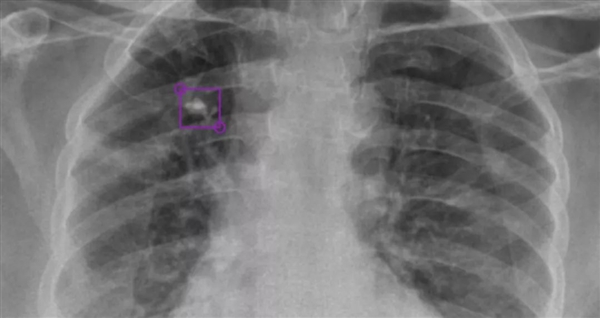

DeepTek AI模型檢測(cè)到的右上葉肺部鈣化結(jié)節(jié)

DeepTek希望通過(guò)AI驅(qū)動(dòng)的放射平臺(tái),大大提升全球在醫(yī)學(xué)影像診斷領(lǐng)域的能力,為此開(kāi)發(fā)了全新的DxTB工具,用來(lái)篩查肺結(jié)核的X射線圖像,并標(biāo)記病例,以供醫(yī)學(xué)專家進(jìn)行優(yōu)先檢查。